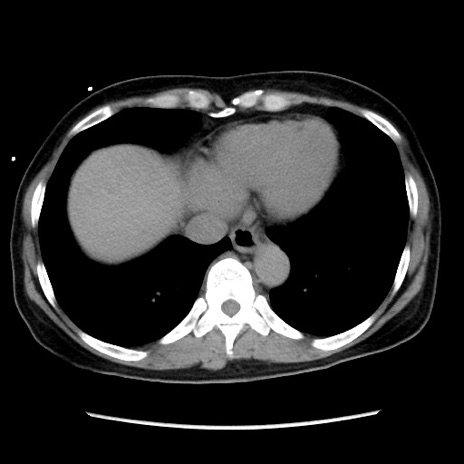

冠状断像

【症例】 50歳代女性

【主訴】 腹痛

【現病歴】前日生レバーを食べた。今朝に排便あり。 昼前に突然発症の腹痛を生じ、当院救急外来を受診した。

【既往歴】 子宮筋腫にてで子宮全摘後

【身体所見】 意識清明、腹部:平坦、軟、下腹部やや左を中心に圧痛・反跳痛あり、筋性防御あり

【データ】WBC 7800、CRP 0.07